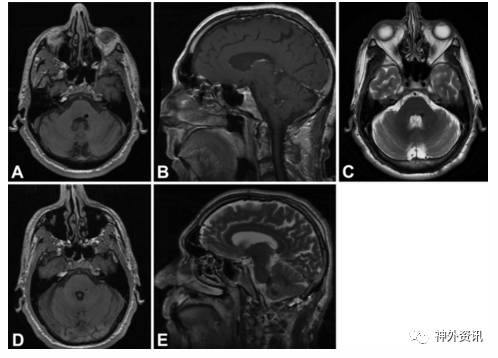

图3. 68岁男性患者的影像学资料。A-C.术前MRI-T1加权轴位、矢状位和T2加权轴位可见位于脑干背侧的海绵状血管畸形,处于面丘同一水平;D、E.术后MRI-T1加权轴位和T2加权矢状位显示病灶全切除。